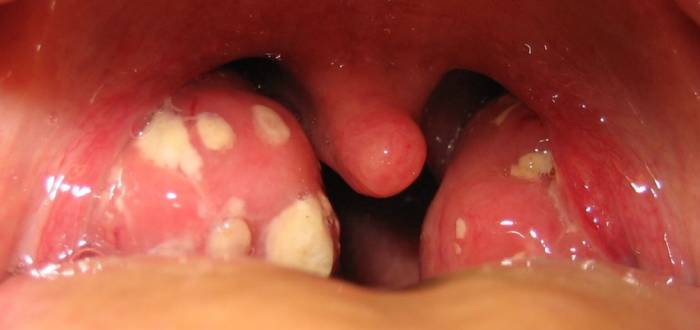

Фактически гнойники на миндалинах – не отдельное заболевание, это всего лишь симптом других болезней, которые поражают горло человека (ангина, фарингит или тонзиллит).

Во время этих заболеваний на миндалинах может появиться одиночный гнойник, или их может быть большее количество. Они бывают разной величины и формы, что зависит от особенностей строения миндалин и характера их поражений. Температура может быть, а может и отсутствовать вовсе.

Гнойники бывают белого или светло желтого окраса. Касательно их места положения: могут находиться за складками органа и тогда увидеть их сможет только врач.

- Лакунарная ангина — на миндалинах появляется белый или желтый налет, скапливающийся в криптах (лакунах). Гнойники могут выходить за пределы лакун и сливаться. Врачи нередко наблюдают миндалины, полностью покрытые гнойным налетом, который легко удаляется, но быстро возвращается без лечения.

- Фолликулярная ангина — характеризуется покраснением и отеком гланд с образованием мелких гнойничков белого или желтого цвета, которые вскрываются самостоятельно.